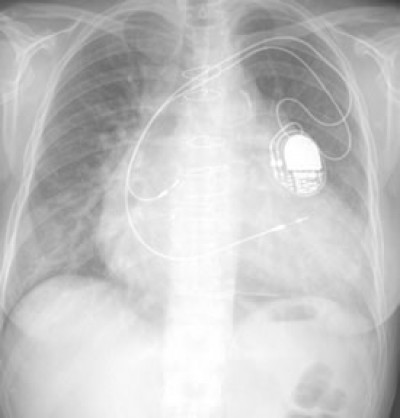

Lastly, this is an X-Ray showing the location and parts and where they are and where they go etc etc…